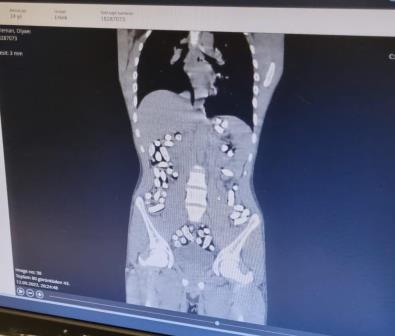

Erzurum-Erzincan kara yolu uygulama noktasında kontrol yapan Erzurum Emniyet Müdürlüğü Narkotik Suçlarla Mücadele Şube Müdürlüğü ekipleri, 10 Eylül’de İran plakalı bir otobüsü durdurdu. Araçta yolcu olarak bulunan Mehdi B., Milad F. ve Siraus G.'nin hareketlerinden şüphelenen polis, röntgen çekimi için hastaneye götürdü. Yapılan muayene ve röntgen çekimi sonrası şüphelilerin uyuşturucuları kapsül haline getirerek yuttukları belirlendi. Hastanede yapılan çalışmayla şüphelilerin midesindeki toplam 210 kapsül içindeki 3 kilo 192 gram Afyon sakızı ile 62 kapsül halinde 709 gram eroin çıkarıldı. Emniyetteki işlemlerinin ardından adliyeye sevk edilen 3 şüpheli 14 Eylül günü tutuklandı.

Narkotik polisi, 12 Eylül’de de aynı uygulama noktasında yaptıkları aramada İran uyruklu Mesoud T. ile Soleman O.'nun çantalarında tokluk hissi veren ve mide bağırsak temizleyici ilaç bulunmasından şüphelendi. Hastanede röntgen filmleri çekilen şahısların 411 kapsül halinde yuttukları 2 kilo 953 gram afyon sakızı çıkarıldı. Adliyeye sevk edilen 2 şüpheli de tutuklanarak cezaevine gönderildi.